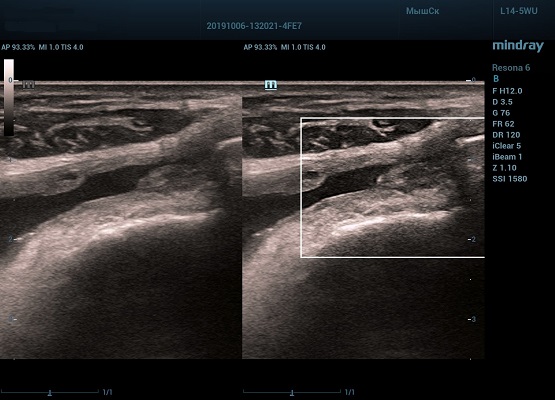

HD Scope позволяет достигать поразительной разрешающей способности выбранной зоны сканирования, при этом улучшая как детализацию, так и контрастность изображения. Помимо пространственного разрешения мы получаем преимущество и по разрешению во времени. Прибор получает огромное количество нативных изображений практически одновременно, и при сборе итоговой картины не происходит смещения объекта под датчиком, а значит и нет размывания изображения. Все участки раздела фаз, каждый контур образования теперь видны, мы все ближе к идеальной картинке.

Как он работает? Особенностью платформы ZST+, на которой построены приборы Mindray Resona, является так называемое многолучевое сканирование. В отличие от обычного датчика, который получает изображение в виде прямого эхо, датчики приборов этой серии проводят многолучевое сканирование каждым элементом с огромной скоростью, получая огромное количество данных. Затем происходит сложная постобработка и сбор из множества «многолучевых» снимков идеальной картинки.

Вторая особенность ультразвуковых машин данной линейки — это изменение расчетных констант распространения ультразвука, таким образом прибор перебирает для каждой ткани свои значения скоростей волны и пересчитывает каждую точку, делая менее выраженным поглощение по глубине. Эти особенности позволили использовать без фокусные технологии сканирования. Функция HD Scope позволяет использовать эти ресурсы для исследование небольшой области, значительно увеличивая качество изображения.